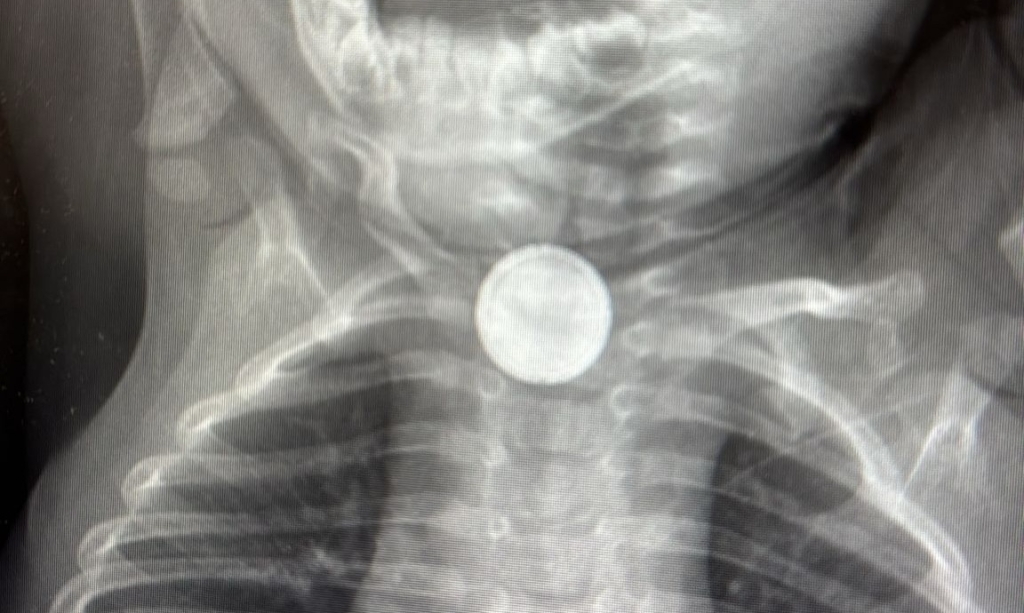

בצילום רנטגן דחוף שבוצע, התגלה גוף זר עגול התקוע בוושט, שאכן נראה כסוללה. מכאן הפך הזמן לקריטי, מכיוון שסוללה התקועה בוושט, עלולה לגרום לנזק מיידי ולעיתים בלתי הפיך.

בעקבות זאת הוכנס התינוק לניתוח חירום, במהלכו הוכנס אל תוך הוושט - בפעולה הנקראת "אסו-פגוסקופיה" - מכשיר דק דמוי צינור, כדי לאתר את הגוף הזר.

לאחר איתורו, נשלפה הסוללה, באמצעות מלקחיים, ע"י ד"ר נתנאל איזנבך, רופא מומחה אא"ג, וד"ר צוף ברסודסקי, אף היא רופאה מהמחלקה.